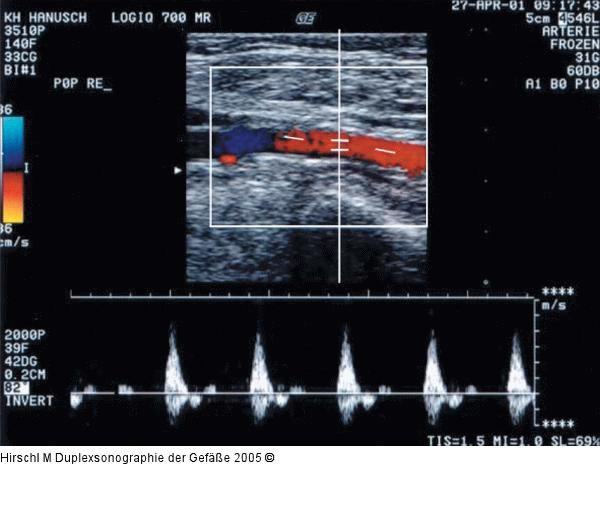

Abbildung 17: Duplexsonographie - Pulsdoppler

Schlecht eingestellter Winkel sowohl des Farb- als auch des Pulsdopplers, daraus resultierend: vor allem beim Pulsdoppler ein Pendelschlag in der Systole. |